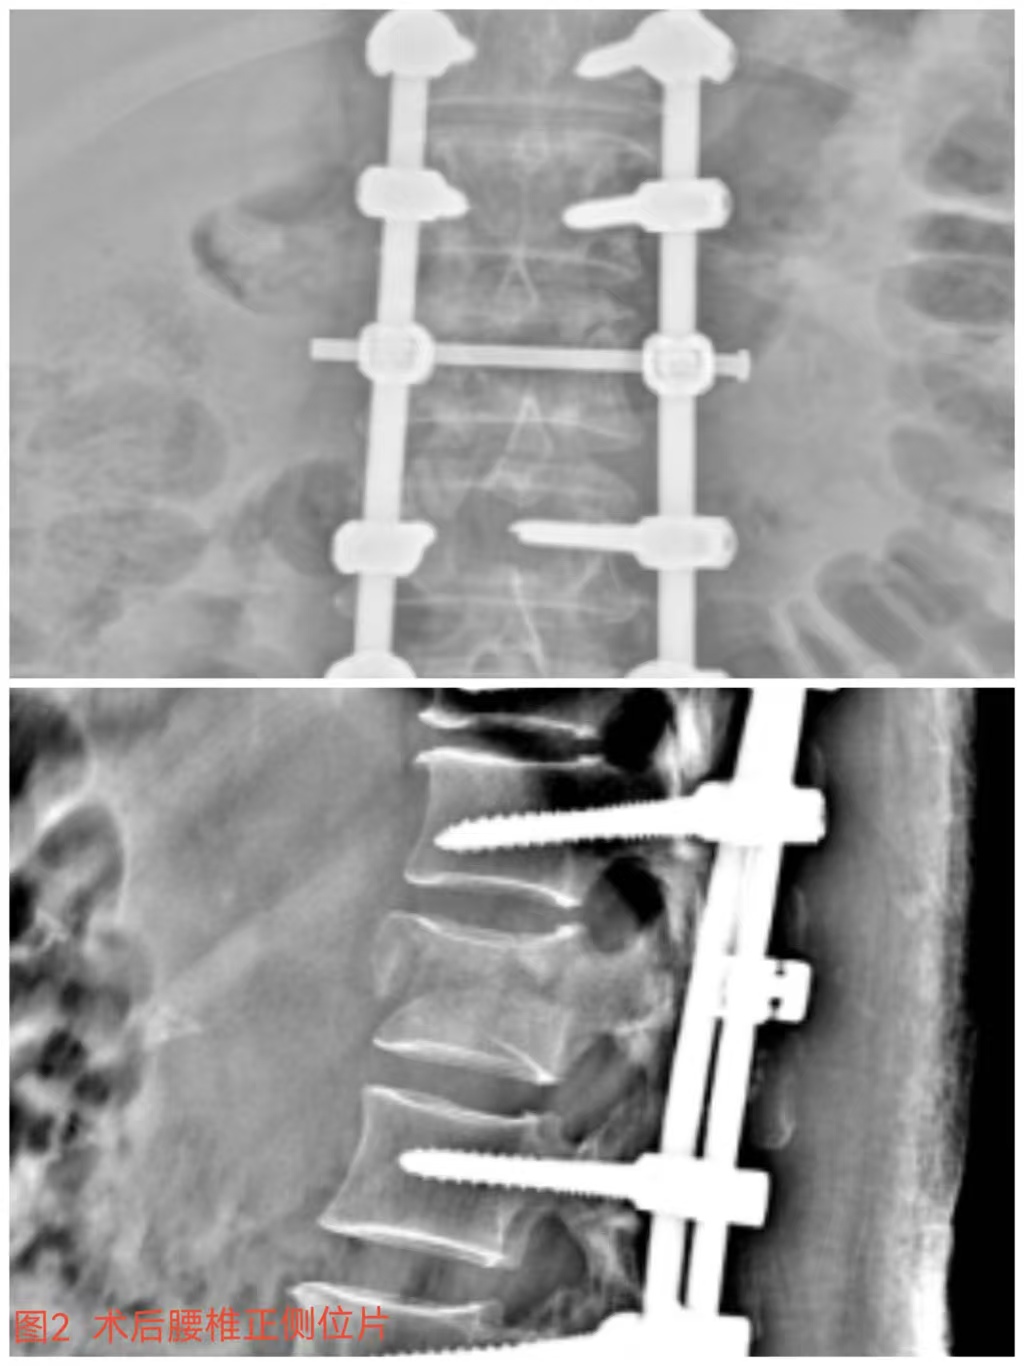

俞德亮副主任医师深知病情的严重性,,,,拖得时间越久,,,,脊髓神经损伤症状越难以恢复,,,,必需掌握住早期减压手术的要害时间窗,,,,紧迫向导创伤骨科医师团队对该病情举行讨论、制订手术方案,,,,并乐成为患者急诊行“L1椎体爆裂性骨折伴截瘫切开椎板切除+椎管探查减压+骨折复位钉棒系统内牢靠术(图2)”,,,,该手术准确扫除对脊髓神经的榨取,,,,并通过椎弓根螺钉内牢靠系统对受损的腰椎提供稳固的支持,,,,为后期的康复创立了优异的条件。。。。